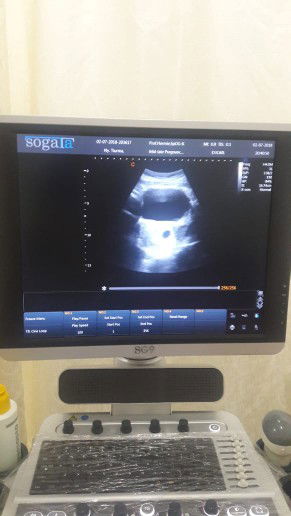

Ini adalah foto usg pertama di kehamilan pertamaku. Dan untuk dapetin foto ini ternyata ga mudah. Kenapa??? Sebagai bumil baru, waktu liat ada dua garis merah di hasil tespek tentunya senang bukan main. Segera aku dan suami bergegas ke dokter kandungan.. dan beruntung banget ketika sampai di RS aku adalah pasien pertama yg datang. wah dapet nomor antrian 1 nih. ? Namun ternyata kesabaranku harus diuji, ketika susternya nanya "baru mau usg pertama ya Bu?" "Iya" "Kalo gitu minum air dulu yg banyak. Ntar kalo udah kebelet pipis, kasih tau saya ya ... nanti ibu langsung masuk" Demikianlah aku harus maksain kerongkonganku nenggak 1.5 liter air dalam waktu 2 menit, dan nunggu sekitar 2,5 jam sampai rasa damai (baca: pee-peace) itu datang.. nyesek karena sambil liatin pasien2 yg baru datang setelahku malah duluan masuk utk diperiksa. Namun rasa sesak di dada itu hilang ketika akhirnya aku ngerasa geli2 pengen pipis tapi kudu ditahan, tiba saatnya giliranku utk masuk diperiksa.. dannn bulatan hitam seukuran telur puyuh yg kulihat di monitor usg itupun mengukir senyuman di bibirku. ? Yasss! Positif! #CeritaHamilTAP Buibuk disini ada yg punya pengalaman yg sama? ?